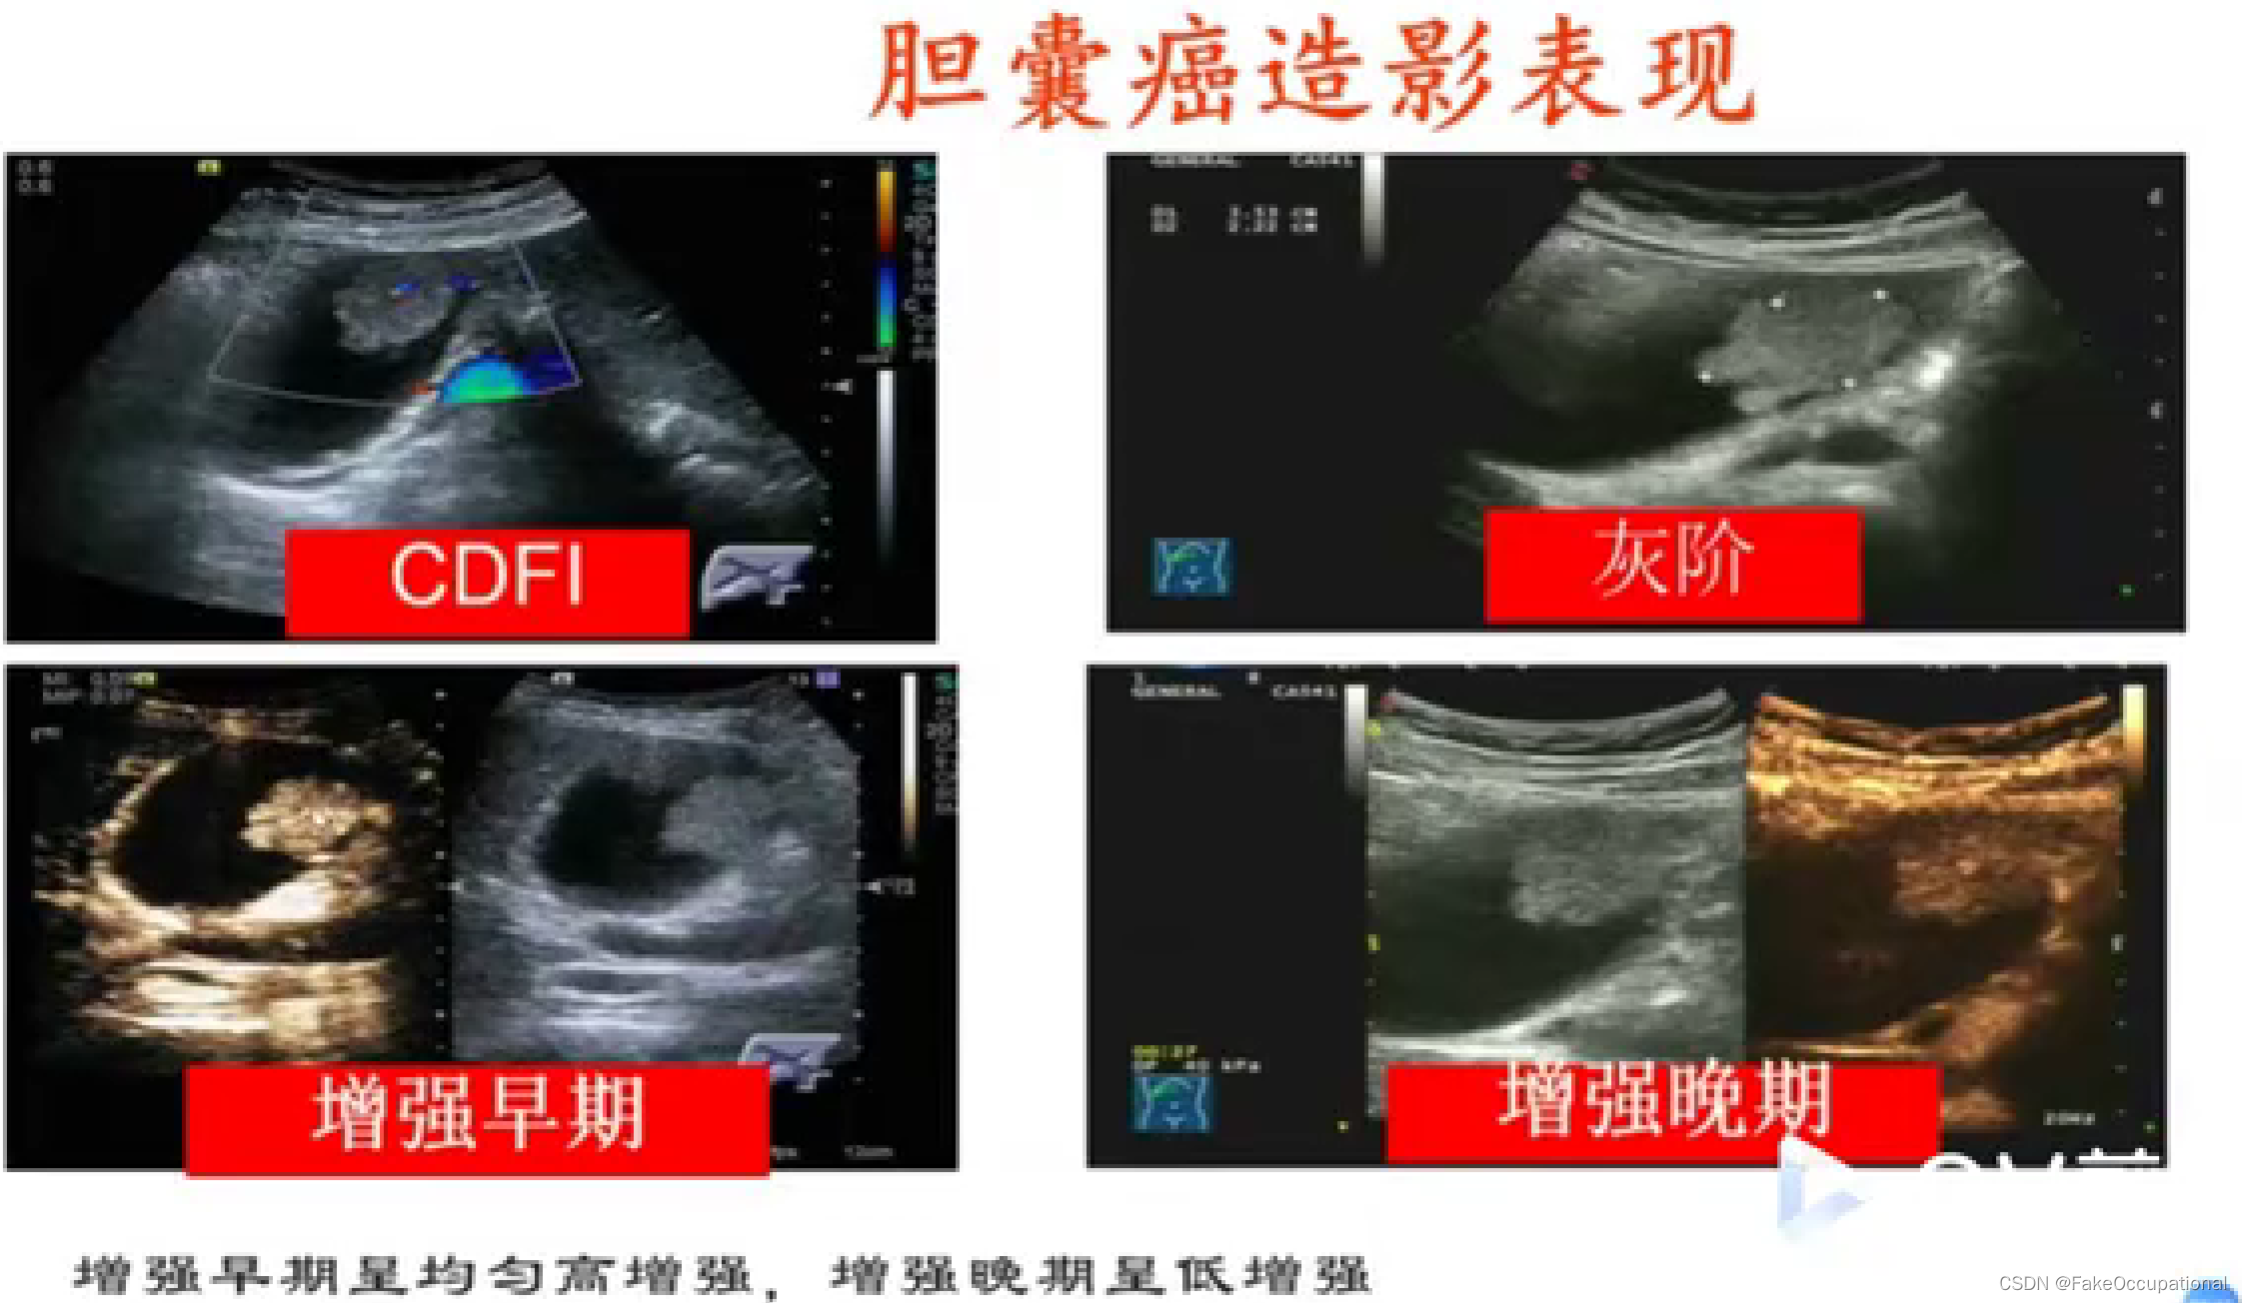

- 彩色编码实时显示血流方向、速度及血流性质:彩色多普勒血流成像(CDFI),彩色多普勒能量图(CDE)

- 超声造影